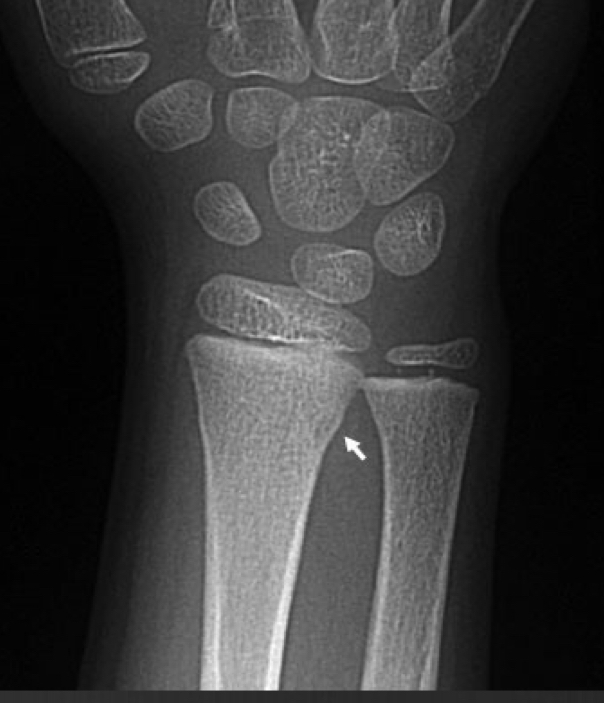

Torus fracture

lacks smooth margin